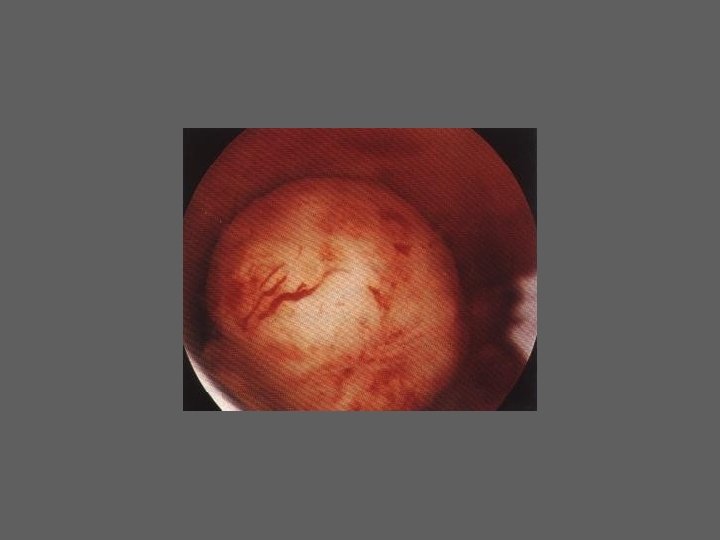

HISTEROSCOPIA - INDICAÇÕES Todas a situações em que se julgue vantajosa uma visualização completa da cavidade uterina, em particular: – Metrorragias – Dismenorreia adquirida – Infertilidade – Abortamentos de repetição e parto pré-termo – HSG anormal – DIU “perdido” – GIFT e ZIFT – Tratamento cirúrgico da patologia intracavitária: ● pólipos, miomas, septos, sinéquias, recessões endometriais ● baixos custos, reduzida morbilidade

HISTEROSCOPIA - MATERIAL CO 2 – Insuflador – Metrorragias max. 100 ml /min p < 100 mm Hg liquido (soro glicosado, dextrano, etc. ) – Fonte de luz fria – Histeroscópio (3, 5, 7 mm) – rígido ou flexível – Bainha e instrumentos cirúrgicos (pinça de biopsia, tesoura, etc.